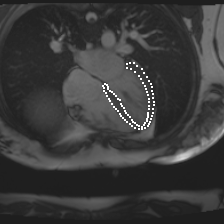

Accurate segmentation and motion estimation of myocardium have always been important in clinic field, which essentially contribute to the downstream diagnosis. However, existing methods cannot always guarantee the shape integrity for myocardium segmentation. In addition, motion estimation requires point correspondence on the myocardium region across different frames. In this paper, we propose a novel end-to-end deep statistic shape model to focus on myocardium segmentation with both shape integrity and boundary correspondence preserving. Specifically, myocardium shapes are represented by a fixed number of points, whose variations are extracted by Principal Component Analysis (PCA). Deep neural network is used to predict the transformation parameters (both affine and deformation), which are then used to warp the mean point cloud to the image domain. Furthermore, a differentiable rendering layer is introduced to incorporate mask supervision into the framework to learn more accurate point clouds. In this way, the proposed method is able to consistently produce anatomically reasonable segmentation mask without post processing. Additionally, the predicted point cloud guarantees boundary correspondence for sequential images, which contributes to the downstream tasks, such as the motion estimation of myocardium. We conduct several experiments to demonstrate the effectiveness of the proposed method on several benchmark datasets.